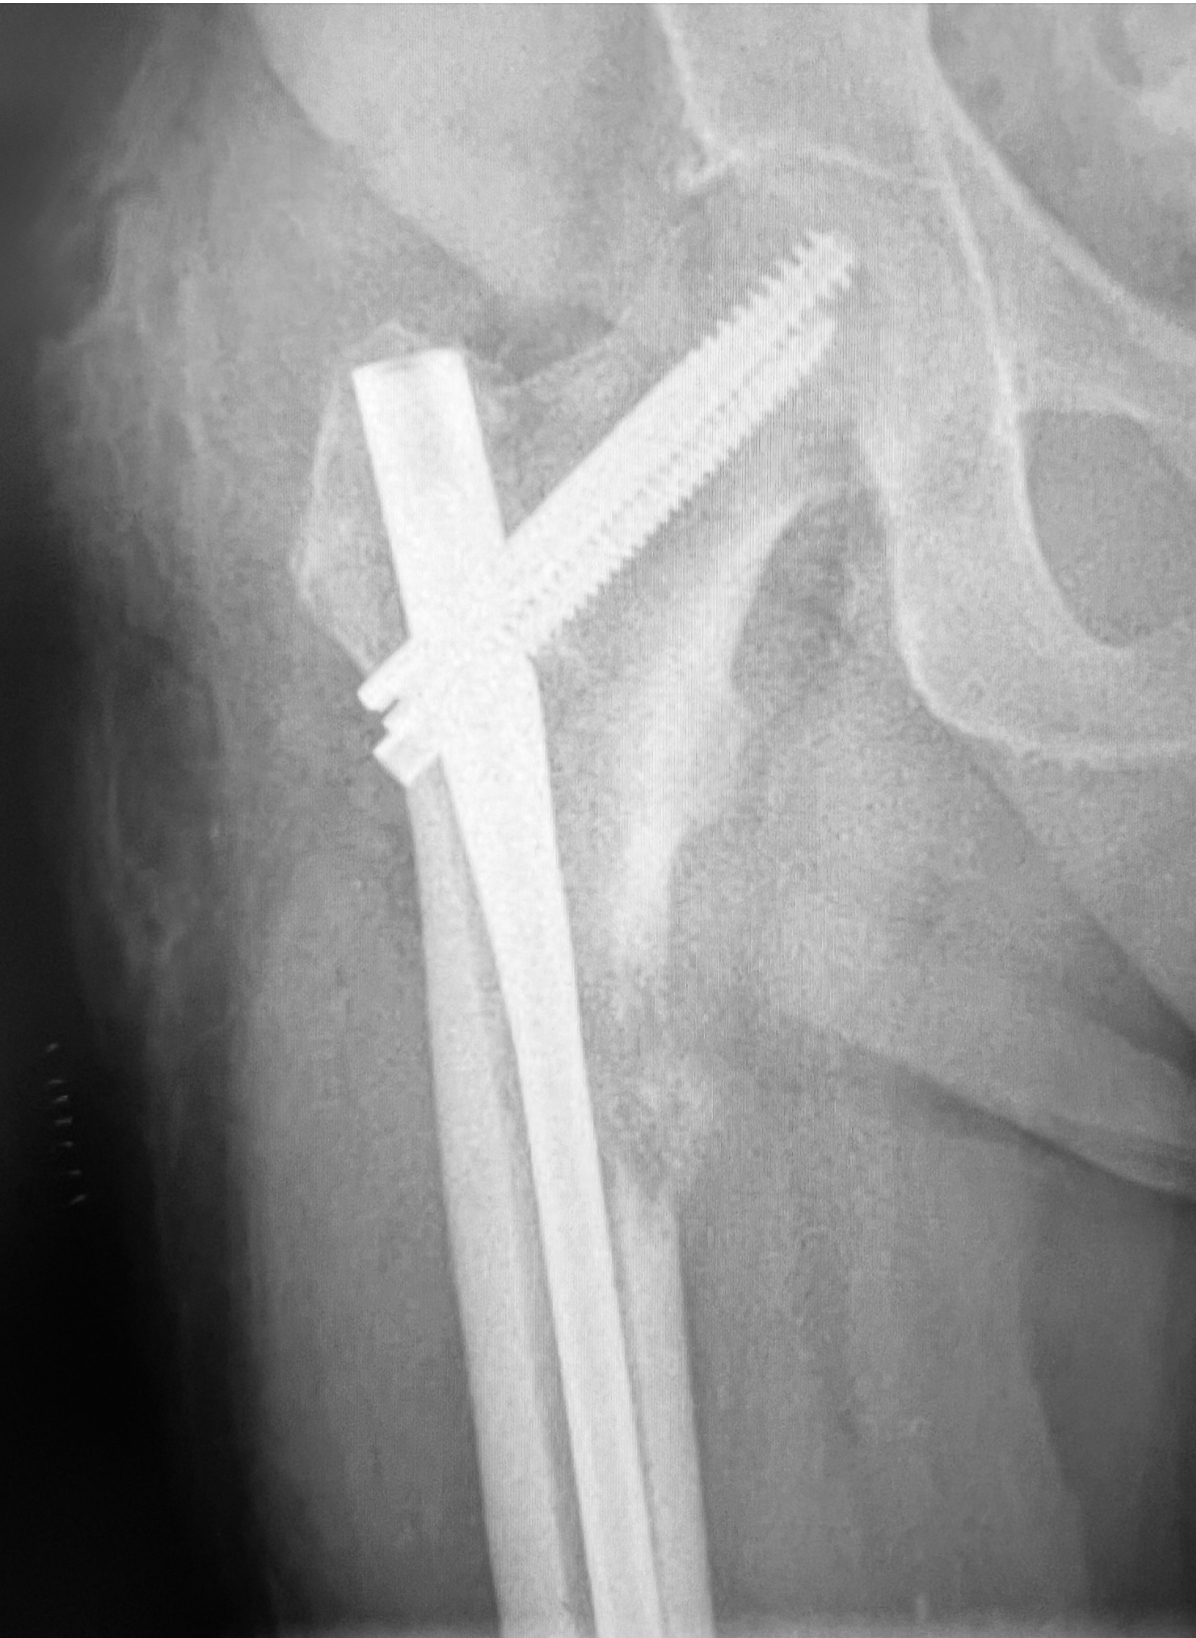

🔹 1. Osteosíntesis profiláctica: prevenir la fractura antes de que ocurra

Cuando la metástasis debilita mucho el hueso, existe riesgo de que se fracture incluso con movimientos cotidianos. En estos casos, podemos colocar un clavo (osteosíntesis profiláctica) para reforzar el hueso y evitar la fractura.

👉 Ejemplo: una metástasis en el fémur que está debilitando más del 50% del hueso.

Metástasis ósea lítica con alto riesgo de fractura patológica

Fijación profiláctica de una metástasis de femur evitando la fractura